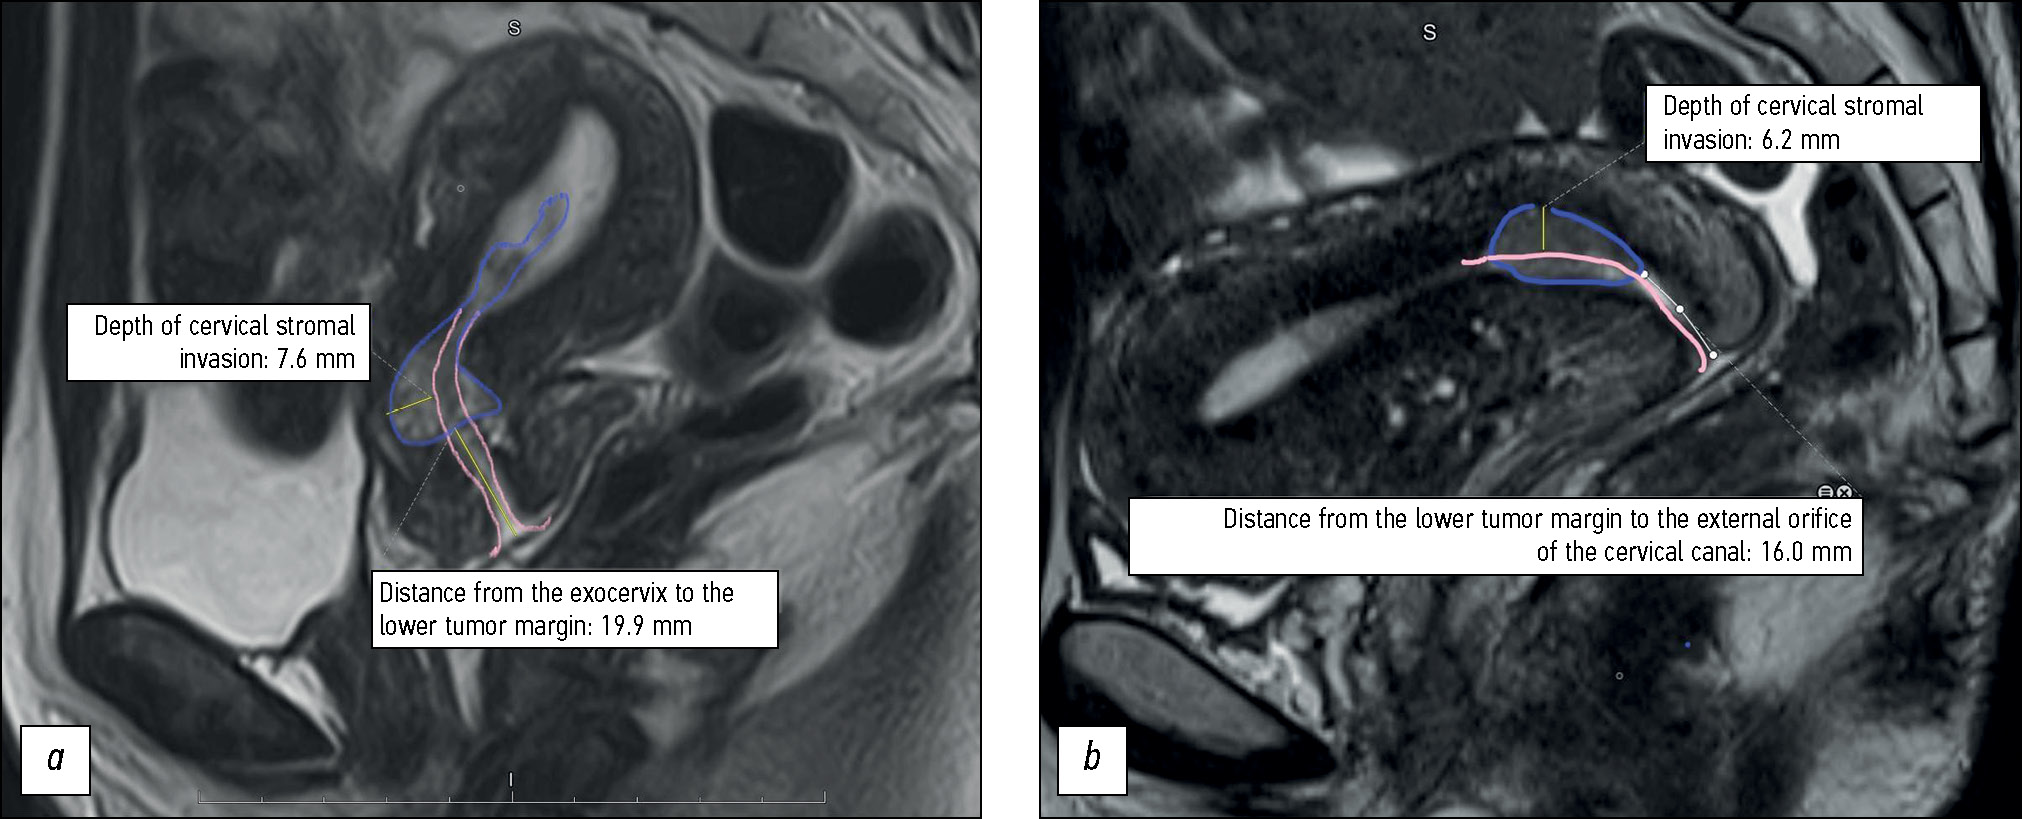

T2-WI MRI data were used to evaluate the size and depth of cervical stromal invasion (Fig. 2); the presence of parametrial invasion; involvement of the internal orifice and isthmus of the uterus, endometrial lining, uterine appendages, and lymph nodes; and the presence of a “feeding pedicle” in the tumor. The tumor pedicle was used to designate the junction between the tumor and uterine wall, considered as the tumor origin, with tumor feeding vessels visualized in the arterial and venous phases of dynamic contrast enhancement.

Fig. 2. An example of measuring the depth of cervical adenocarcinoma invasion into the stroma and the distance from the tumor to the exocervix: (а) the tumor is located in the upper third of the cervix, has a depth of invasion of 8 mm and is located at a distance of 20 mm from the exocervix; (b) the tumor is located in the upper third and middle third of the cervix, has a depth of invasion of 6 mm and is located at a distance of 16 mm from the exocervix. The tumor is outlined with a purple line, the endocervical canal is marked with pink lines. Conclusion of the pathomorphological study: endocervical adenocarcinoma of the cervix grade 2; depth of invasion into the cervical stroma 5 mm (less than 1/2 the thickness of the cervical wall); lymphovascular invasion was detected; the tumor grows into the internal os; endometrium in the secretion phase.